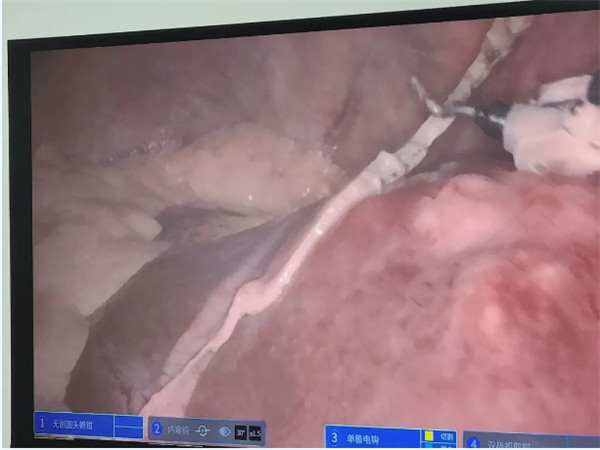

肝膽胰脾外科副主任金上博自得知王師傅病情后非常重視,多次同各個(gè)相關(guān)科室聯(lián)系并且與患者家屬討論治療方案。為進(jìn)一步降低風(fēng)險(xiǎn),取得更好的手術(shù)效果,考慮機(jī)器人輔助手術(shù)。手術(shù)機(jī)器人技術(shù)具有裸眼3D功能,放大10倍的視覺(jué),創(chuàng)傷更小,微創(chuàng)手術(shù)指征更廣,術(shù)中對(duì)機(jī)體的損傷大大縮小,機(jī)器臂操作更為精準(zhǔn),靈活。應(yīng)用同樣的幾個(gè)孔就可以在切除肝臟腫瘤后,利用原來(lái)的孔將機(jī)械臂操作盤(pán)向下旋轉(zhuǎn)180度去切除下腹部結(jié)腸的腫瘤,并不增加操作孔和手術(shù)難度,可以既減少手術(shù)時(shí)間和困難,又保證手術(shù)安全。與家屬商議后,最終決定同普外科副主任葸根一起為王師傅實(shí)施機(jī)器人輔助的肝部分切除聯(lián)合乙狀結(jié)腸癌根治術(shù)。

術(shù)中,兩個(gè)科室交叉手術(shù),肝膽胰脾外科先完成肝部分切除術(shù),再由普外科進(jìn)行乙狀結(jié)腸癌根治術(shù),最后兩個(gè)科室一起合作,完成剩余部分。

正如術(shù)前所料,相較于傳統(tǒng)的開(kāi)腹手術(shù)及腹腔鏡手術(shù),手術(shù)機(jī)器人利用操作靈活便利和創(chuàng)傷小的優(yōu)點(diǎn),大大降低了術(shù)中出血的風(fēng)險(xiǎn),裸眼3D的視野也改善了術(shù)野暴露不佳的情況。兩科室及麻醉科醫(yī)生有條不紊的配合下,手術(shù)順利完成,術(shù)中出血量不多,各項(xiàng)生命指標(biāo)全術(shù)程非常平穩(wěn)。術(shù)后王師傅恢復(fù)順利,很快康復(fù)出院。我院此次開(kāi)展機(jī)器人聯(lián)合手術(shù)省內(nèi)未見(jiàn)報(bào)道。